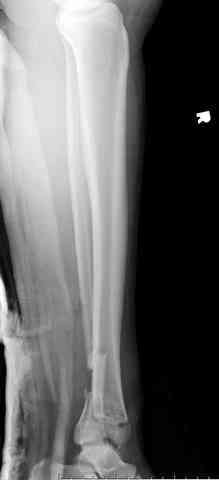

Здесь выставлена пара случаев перелома пилона, оба

случая леченные этапным наружным фиксатором.

Второй случай фиксирован аппаратом Илизарова.